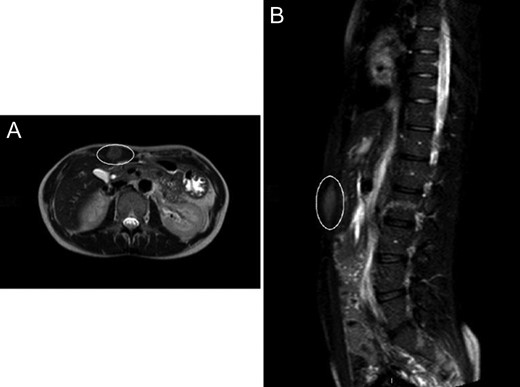

A 37-year-old female, otherwise healthy patient, presented to observation with a 3-month history of a mass in the upper right side of the abdomen, which has been gradually increasing in size, and no other associated symptoms. Past medical history was remarkable for atrial septal defect closure at the age of ten, but no previous abdominal surgeries or trauma. Patient did not smoke, drink alcohol or took any medication. During the physical examination, inspection showed a tattoo on the right side of the umbilicus (Fig. 1A); palpation at the same level revealed a painless and firm mass of 5 × 4 cm2 approximately, with not easily definable edges. Ultrasonography showed a 4 cm2 mass with no clear margins. Abdominal magnetic resonance (MRI) was subsequently performed describing a 17 × 19 × 50 mm3 mass confined into the rectus abdominis (Fig. 2A and B). Needle biopsy samples were taken, and pathology report confirmed the diagnosis of a desmoid tumour.

(A) Abdominal CT showing the desmoid tumour within the abdominal wall. (B) Abdominal CT scan showing lateral view of the desmoid tumour.

The surgery for the mass removal was performed under general anaesthesia and the incision was placed in the upper edge of the tattoo, just above the tumour localization (Fig. 1). A segment of 7 × 5 × 3 cm3 was resected from the rectus abdominis. Abdominal wall was subsequently reconstructed with primary fascial closure reinforced with underlay polypropylene mesh. Local bupivacaine infusion catheter was placed for pain control [6]. Abdominal suture was carried out in three layers abdominal fascia using Vicryl 3-0 for abdominal fascia and dermis, and skin with single stiches prolene 4-0 (Fig. 1B). Wound healing was uneventful and the specimen confirmed a desmoid tumour, without mitotic or necrotic features, radically excised. At three months follow-up the scar was difficult to notice because of the tattoo. At 2-year follow-up, the patient was satisfied with his tattoo scar, while no tumour recurrence revealed by MRI, either abdominal hernia nor bulging could be detectable (Fig. 3B).